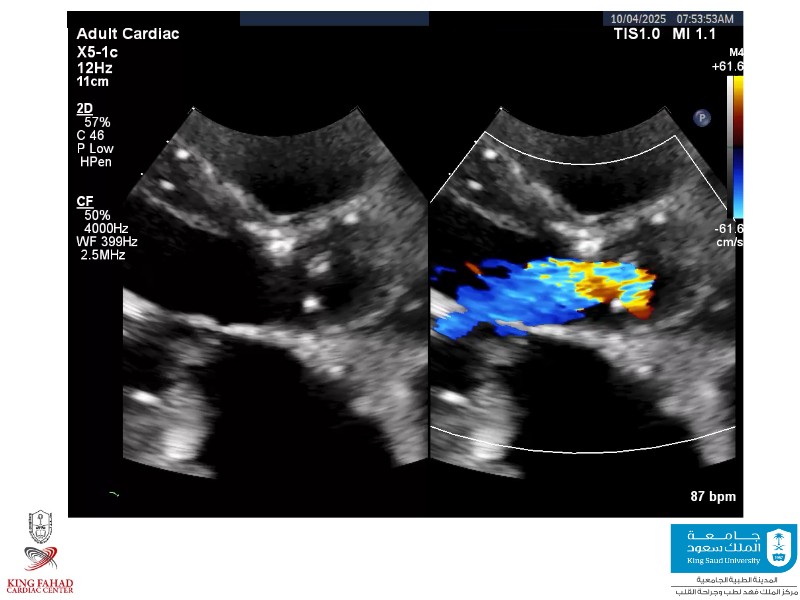

This session helps you anticipate and address complex scenarios such as mitral valve-in-valve, TAV-in-SAV, and valve-in-valve-in-valve procedures. Learn from expert case discussions that explore procedural strategies, technical challenges, and best practices to optimize outcomes in redo structural heart interventions.